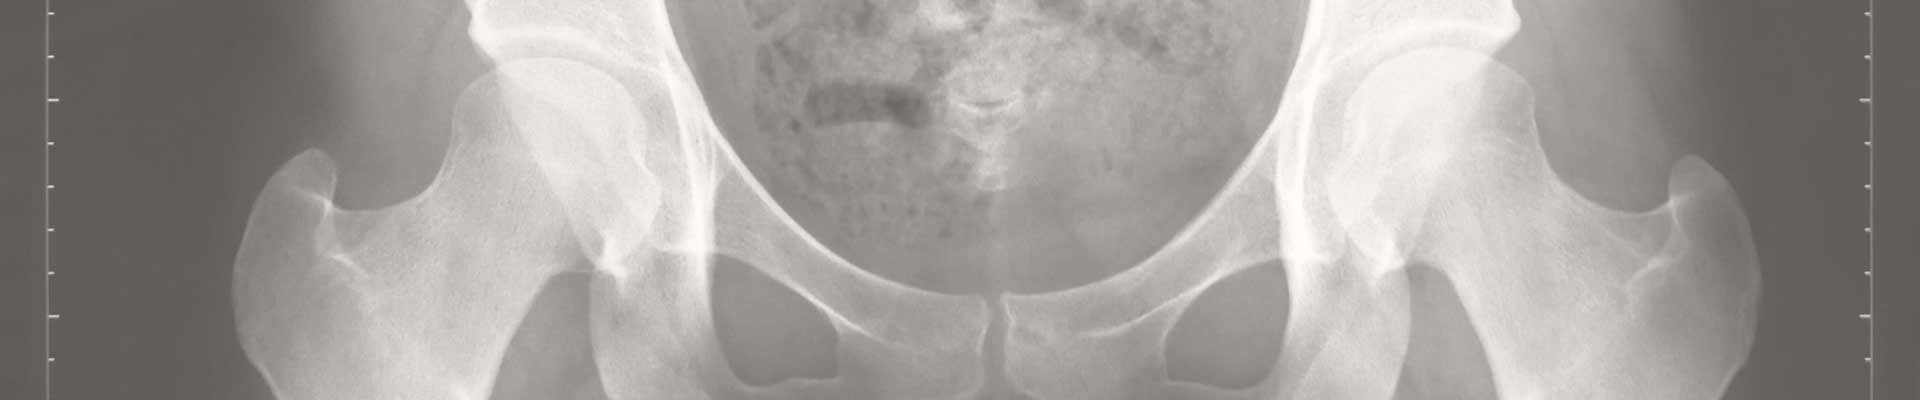

Das Hüftgelenk besteht aus der Hüftpfanne des Beckens und dem Hüftkopf des Oberschenkelknochens. Diese beiden Strukturen bilden zusammen ein Kugelgelenk, das beim Neugeborenen jedoch noch nicht vollständig ausgereift ist. Die Hüftpfanne ist in den ersten Lebensmonaten relativ weich, besteht aus Knorpelmaterial und muss sich im Verlauf weiter vertiefen, um dem Hüftkopf ausreichenden Halt zu bieten.

Von einer Hüftdysplasie spricht man, wenn die Hüftpfanne nicht ausreichend tief oder stabil ausgebildet ist. Dadurch liegt der Hüftkopf nicht vollständig in der Pfanne. Diese sogenannte „Reifestörung“ kann unterschiedlich ausgeprägt sein – von leichter Unreife bis zur vollständigen Instabilität oder Luxation, bei der der Hüftkopf aus der Pfanne des Gelenks herausgleitet.

Was zeigt der Ultraschall?

Im Ultraschall wird die Hüftpfanne anhand bestimmter Winkel vermessen und entsprechend dem Graf-System klassifiziert: